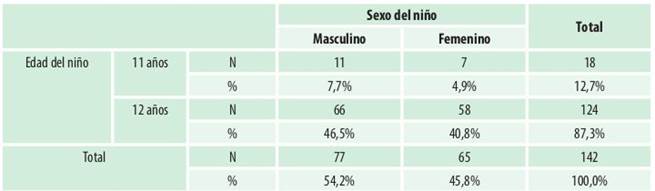

De la muestra de 142 niños el 12,7% fueron niños de 11 años y el 87,3% de 12 años. Con respecto al sexo el 54,2% fueron niños y el 45,8% niñas (Tabla 2).